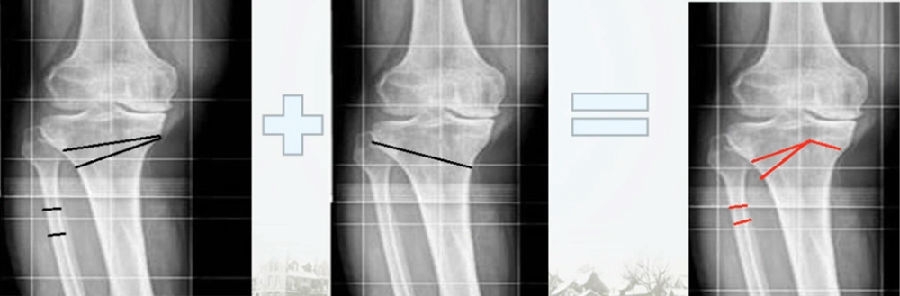

通过MAT测量全长片和内外侧应力位片,可以明确的测量出畸形的来源是股骨还是胫骨,有没有关节内磨损和韧带松弛。

MCOA病例,对线异常来源多个因素:胫骨畸形(MPTA异常),股骨形(mLDFA异常),胫骨平台塌陷,LCL松弛,内侧关节软骨丢失造成关节线不等宽等。MAT可以确定其中每种成分;应力下拍片,确定JLCA的关节松弛成分。关节软骨丢失占JLCA 3度,LCL松弛占JLCA 4度。

2、如何根据内侧间隙确定目标力线?

根据膝关节内侧间室模式程度选择个体化的目标力线。

关节间隙正常:目标MAD=0

关节间隙减少1/3:目标MAD =1/3Fujisawa

关节间隙减少2/3:目标MAD =2/3Fujisawa

关节间隙消失:目标MAD =3/3Fujisawa